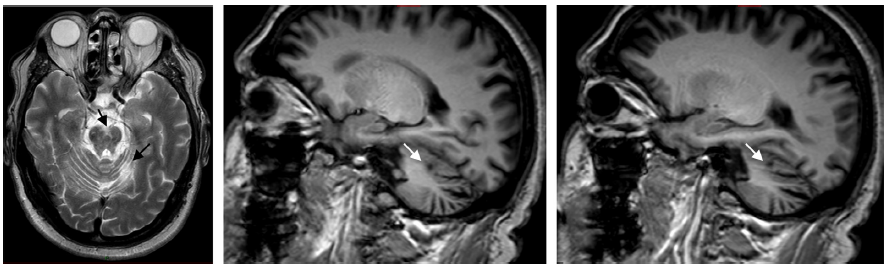

当存在糖尿病

或高血压

等心血管危险因素时,血管原因可能是急性小脑综合征的主要原因(图 1),并且血管病变可导致小脑实质部分萎缩(图 2)。

图 1 患有多种心血管危险因素的患者出现后颅窝多发性卒中。左:头颅MRI T2加权序列图像可见脑干和小脑实质存在高信号病灶(箭头)。中右:头颅MRI T1加权序列图像可见低信号病灶(箭头)。

图 2 血管性小脑病变。左:头颅MRI T2加权序列图像可见右侧小脑中脚急性血管病变。中:头颅MRI T2加权序列冠状位图像显示8年后同侧小脑半球萎缩。右:发病9年后随访的头颅MRI FLAIR序列图像显示小脑中胶异常信号和萎缩。